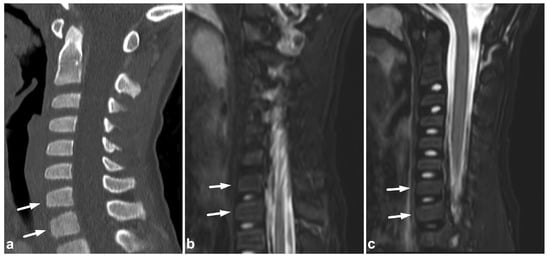

3.1. Compression Fractures

Compression fractures may occur in any spinal segment. Over 80% of these injuries in children affect more than one level [26,27]. Compressions are often non-junctional [26]. MRI displays compression fractures and vertebral body contusions even without visible structural height loss (Figure 1). In burst fractures, MRI enables an instant assessment of concurrent medullary injuries and spinal canal hematomas (Figure 2). Usually, burst fractures are primarily seen in whole-body trauma CT performed due to high-energy injury mechanisms.

Figure 1.

(a) Sagittal T2-weighted. (b) Sagittal T1-weighted. (c) Sagittal STIR. A 9-year-old female, emergency MRI after a horseback riding accident. MRI demonstrates traumatic changes in vertebral bodies Th3–Th9, of which Th5, Th7, and Th8 have structural compressions (arrows). Th3, Th4, Th6, and Th9 have contusions without visible height loss (arrowheads).